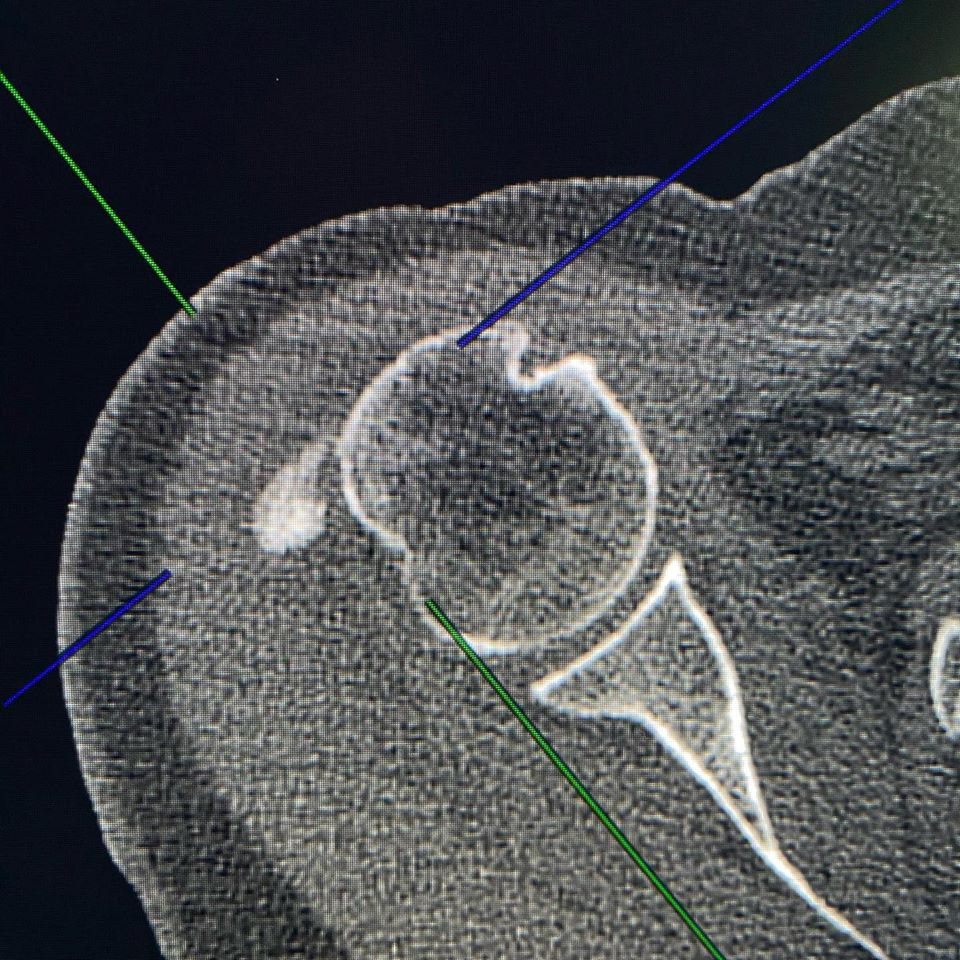

Calcific Bursitis! Hydroxyapatite deposition disease (HADD) is characterized by accumulation of crystals/calcium within articulations and/or in a peri-articular distribution. We commonly see HADD at the rotator cuff tendons, which is usually asymptomatic. However, when shoulder pain is related to the HADD seen on imaging studies, then we make the diagnosis of calcific tendinopathy. In the shoulder we can also see HADD within the subdeltoid/subacromial bursa (calcific bursitis) and within the glenohumeral joint (also known as Milwaukee’s shoulder). A paper published on 1931 argued that “calcific bursitis” was a misnomer, given the belief that the calcium in bursitis isn’t actually deposited in the walls of the bursa but rather shed from the adjacent tendon. Almost 50 years later, the pathophysiology of HADD is still not well understood. Regardless, most radiologists will distinguish the precise location of the Hydroxyapatite deposition, which is easy to determine on imaging studies – tendon > bursa > intra-articular. The treatment and prognosis varies depending on location, so be precise in your dictation! 😉 Also, image guided barbotage of calcific bursitis is usually technically easier than with calcific tendinopathy. #mskrad #mskradiology #radres #radtech #radiologystudent #radiologia #barbotage #calcifictendonitis #hadd #msk🧞♂️